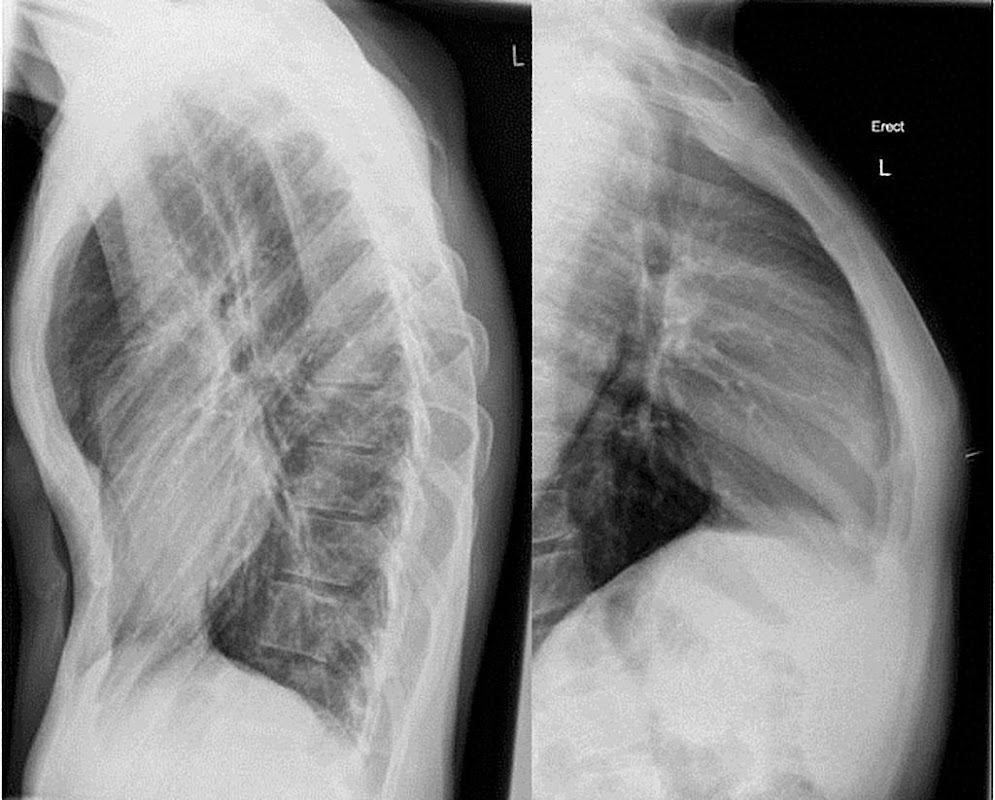

Perform a simulation of X-ray scanner (Prank). Thanks to the camera you can create the effect of X-ray vision of parts of your body such as the hand or foot.

X-ray camera is a simulation game that allows you to make a ray scan as if it were a real one in order to see the bones of a part of your body instantly using your rear camera. Download for free and enjoy the app with your friends and family during this holiday season.